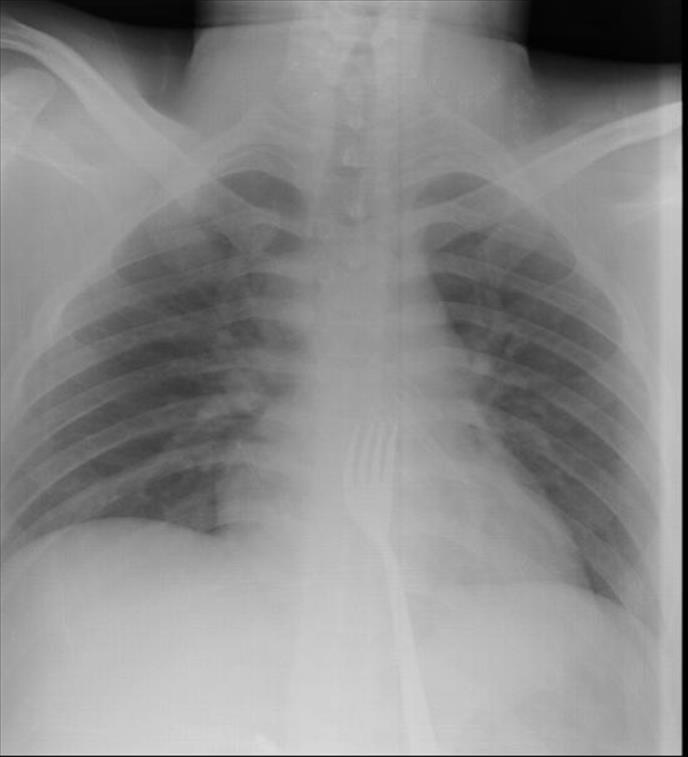

Mladić O. A. imao je velike bolove u stomaku i zatražio je pomoć na Univerzitetskom kliničkom centru. Nespretni 20-godišnjak je lekarima kazao da misli da je progutao viljušku, zbog čega je podvrgnut rendgen snimanju.

Na snimku je uočena metalna viljuška duga 15 centimetara, koju su lekari potom odstranili iz tela. Hirurg Mehmet Erikoglu je kako je sreća da je mladić viljušku progutao "naopačke" pa glatka strana drške nije napravila veća oštećenja pri prolasku kroz jednjak.